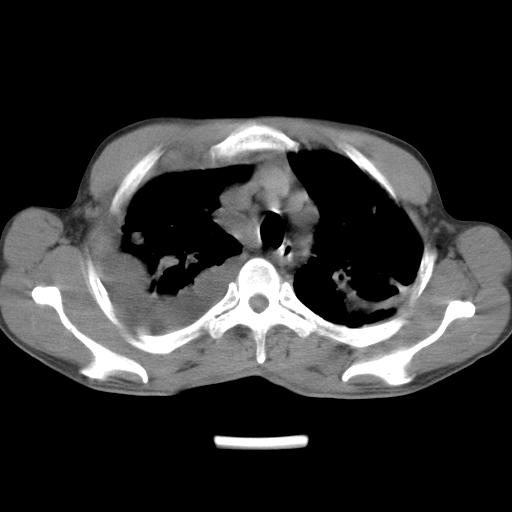

男性,44岁,结核病史多年。现胸闷气短,咳嗽,偶咳血。

右侧胸腔积液

右肺下叶不张

双肺多发结节影最分空洞形成考虑占位不除外结核

双肺陈旧性病变

1、右侧大量胸腔积液伴右肺压缩性膨胀不全,建议抽液治疗后复查 2、两肺继发性tb伴空洞形成。

1)两肺继发性肺结核伴空洞形成,左肺多发性结核球。2)右侧大量胸腔积液伴右肺部分膨胀不全。3)纵隔淋巴结肿大。